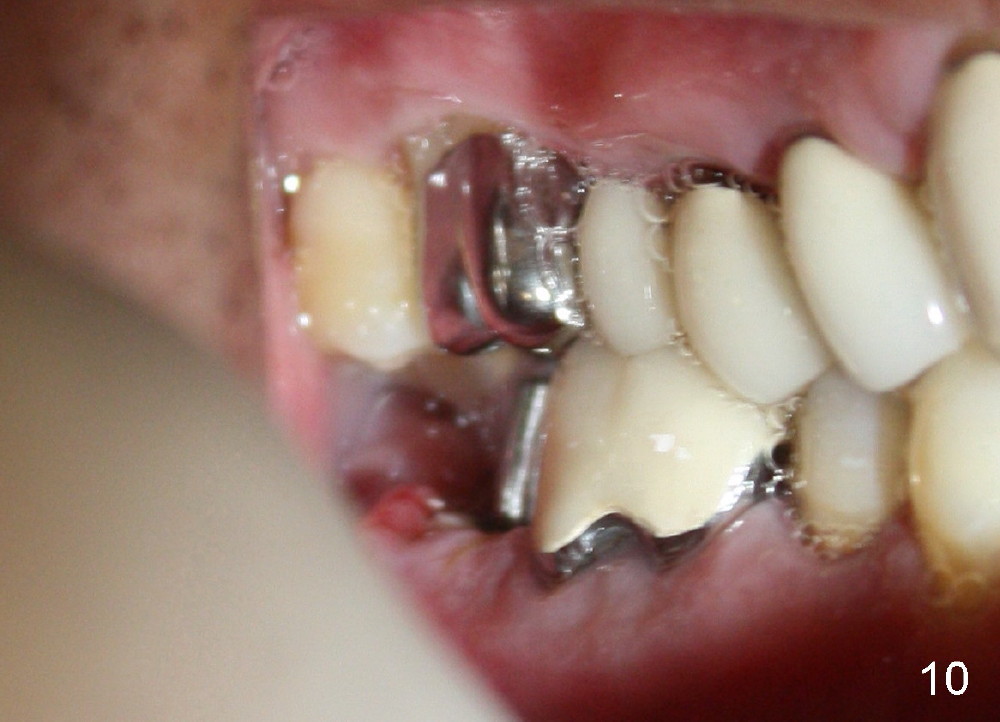

A 51-year-old man has experienced pain and swelling in the lower right 2nd molar for 7 months (Fig.1, P: post in the mesial root; <: gutta percha inserted into a buccal fistula). Fig.2 is taken immediately before extraction (<: purulent discharge from the mesiobuccal fistula) and immediate implant (Fig.3 implant design: 7x14 mm). A vertical root fracture is noted in the mesial root (Fig.4: lingual view). The septum is in fact absent, as compared to Fig.1. The mesiobuccal plate is low; the osteotomy starts lingual to the center of the socket. Fig.5 shows a 4.5x17 mm tap in place: approximately 3.5 mm in the new bone (~2.5 mm from the inferior alveolar canal). When a 7x17 mm tap (14 mm from the gingival margin) is placed in the socket, it looks relatively small. Fig.6 shows a 8x14 mm implant in place with a small gap distally. Mineralized cancellous allograft and Osteogen mixture is placed mainly buccally, followed by a thin strip of collagen dressing and sutures (Fig.7); an abutment (A) is placed to keep perio dressing in place. The perio dressing does not stay long. The buccal portion dislodges by itself 5 days postop. The lingual portion is removed in clinic. New dressing is going to be re-applied, because the buccal wound has not completely healed (Fig.8 <, albeit asymptomatic) with partial exposure of the bone graft (*). Why is the dressing lost so early? The abutment is not long enough; there is plenty of occlusal clearance (Fig.9 arrows). A longer abutment is used to increase mechanical retention for perio dressing (Fig.10). By the time the second perio dressing dislodges, the wound has healed (Fig.11, 13 days postop).